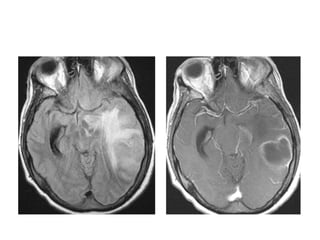

Perinatal (congenital) HIV

–Perinatal transmission – m.c. route

–Only 1/3rd of infected mother can transmit.

–CNS symptoms – HIV encephalitis

• Opportunistic infections & tumors relatively rare, die before 1yr

–NECT – Diffuse cerebral atrophy (nearly 90% cases)

- Basal ganglia calcifications(1/3rd cases)

- Hemorrhage (thrombocytopenia)

–MRI- cerebral atrophy

-Foci of increased SI on T2WI in peripheral & deep white

matter.

mineralizing microangiopathy.

Axial NECT scan in a 5-year-old child with congenital HIV shows 1)bilateral symmetric calcifications in

the basal ganglia and the subcortical white matter . 2). Axial NECT scan in the same patient

shows fairly symmetric punctate and curvilinear calcifications at the gray-white matter junctions

caused by mineralizing microangiopathy.